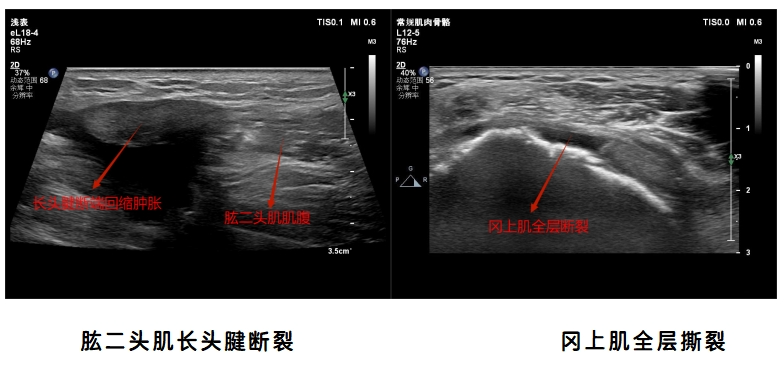

让我们一起看一下肌骨超声图像吧

1.肩关节超声检查:肩袖损伤、肌腱病、粘连性关节囊炎(肩周炎)、肱二头肌长头腱肌腱炎及脱位、肱二头肌断裂、肩锁关节炎等。